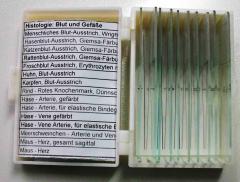

prep15blood = Histologie: Blut und Gefäße Menschlicher Blut-Ausstrich (Wright-Färbung), Hasenblut-, Katzenblut- und Rattenblut-Ausstriche (alle 3 Giemsa-Färbung), Froschblut Ausstrich (Erythrozyten mit Zellkern), Blut-Ausstriche (Karpfen, Frosch, Huhn), Rotes Knochenmark vom Rind (Dünnschnitt), Hase (Arterie, einfach bzw. für elastische Bindegewebsfasern gefärbt), nochmal Hase (Vene, einfach bzw. für elastische Bindegewebsfasern gefärbt), Meerschweinchen (Arterie und Vene auf einem Schnitt), Maus (Herz, gesamt sagittal) (Bild: links 3. von oben)

prep15blood = Histologie: Blut und Gefäße Menschlicher Blut-Ausstrich (Wright-Färbung), Hasenblut-, Katzenblut- und Rattenblut-Ausstriche (alle 3 Giemsa-Färbung), Froschblut Ausstrich (Erythrozyten mit Zellkern), Blut-Ausstriche (Karpfen, Frosch, Huhn), Rotes Knochenmark vom Rind (Dünnschnitt), Hase (Arterie, einfach bzw. für elastische Bindegewebsfasern gefärbt), nochmal Hase (Vene, einfach bzw. für elastische Bindegewebsfasern gefärbt), Meerschweinchen (Arterie und Vene auf einem Schnitt), Maus (Herz, gesamt sagittal) (Bild: links 3. von oben)